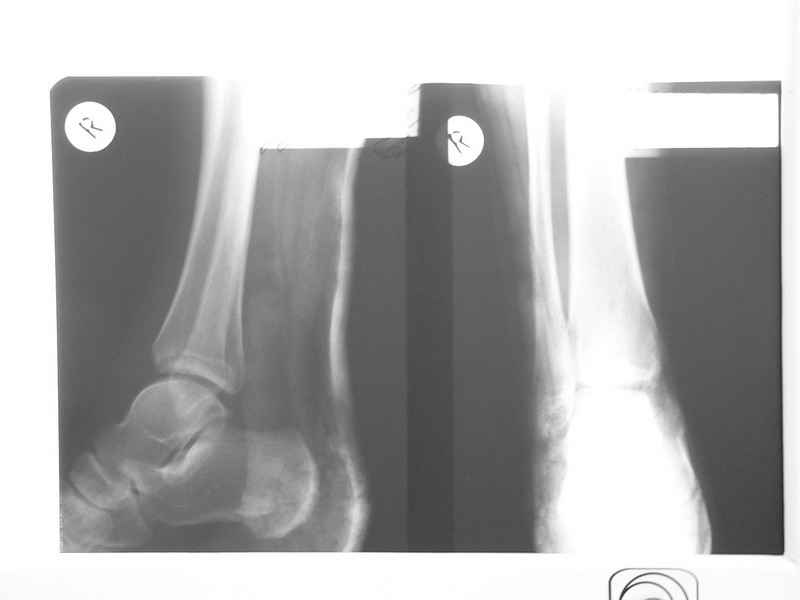

Совершенно верно был такой Пациент парень 29 лет. Только не 2 года а 4 года назад. Лечение растянулось на 2 этапа. На момент сообщения наложил окончатую гипсовую повязку, мазевые повязки, грануляции, закрыл свободной кожной пластикой. Через 2 месяца рана закрылась рубцом, гипс снял отправил на ЛФК. В течение года появлялся дважды - все ОК, нестабильности в суставе не было. Пациент работник УВД - его даже не комисовали. Обратился через 2 года после повторной травмы (опять мотоцикл) - открылся свищ в области медиальной лодыжки. Проведена операция - санация, рубец иссечен, пластика суральным лоскутом - состоятельная. Аппарат Илизарова на 2 месяца. Аппарат демонтировали опять ЛФК - Нестабильности в суставе нет, до сих пор трудится в органах... Опять подумывает о покупке мотоцикла.

К сожалению снимки нашел только после пластики. Р-гр где-то утерял посмотрю не работе.